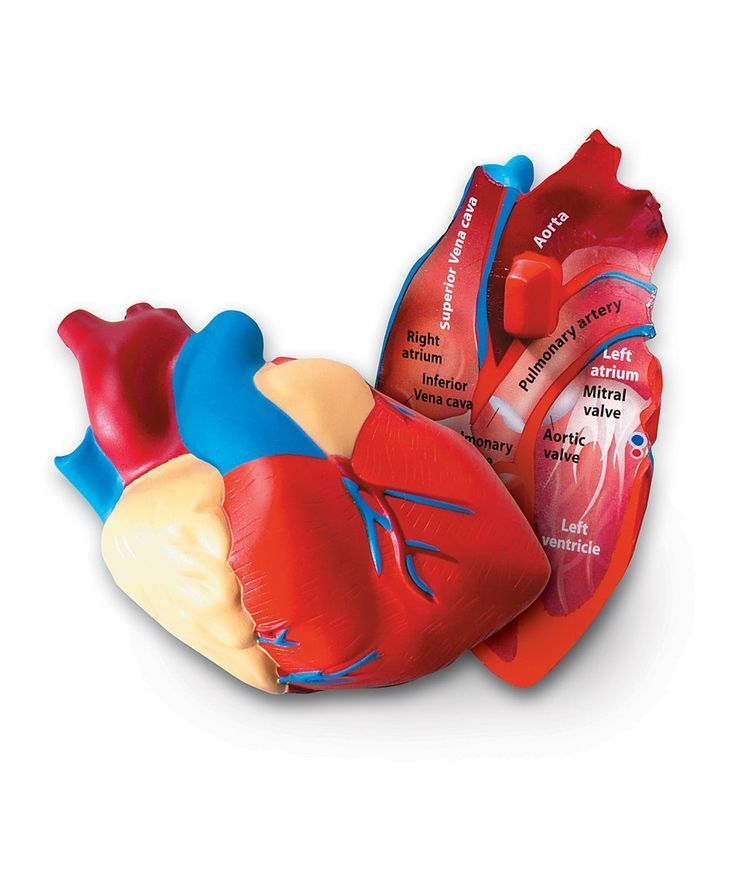

Фотографии и 3D-модели анатомии сердца человека